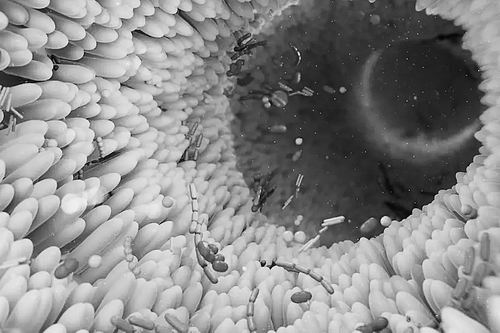

生活在肠道内的数万亿个微生物,对人体健康有着举足轻重的影响。图片来源:THOM LEACH